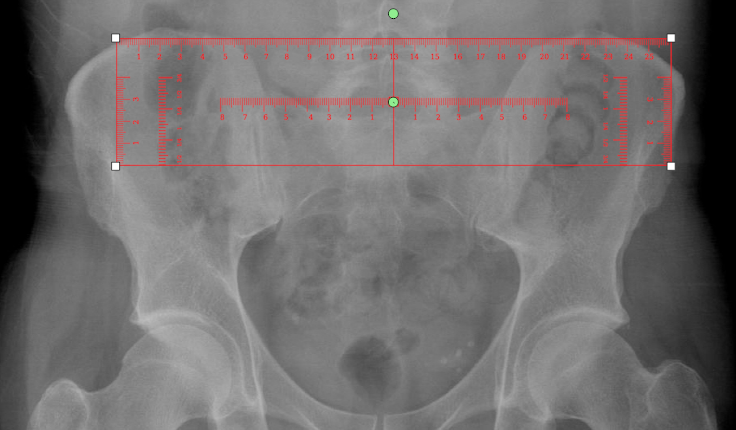

9.5.14. Gonstead Ruler Template

The Gonstead ruler template is used to find the . Follow the instructions below to use this tool:

1.      Select the ‘Gonstead ruler template’ from the advanced section of the chiropractic toolbox

2.      Click on the image and the template will appear on the image.

3.      To move the template: click on the template and drag it to the desired location.

4.      To rotate the template: click on the green point and a wheel will appear for you to click and rotate the template.

An example of this template is shown below: